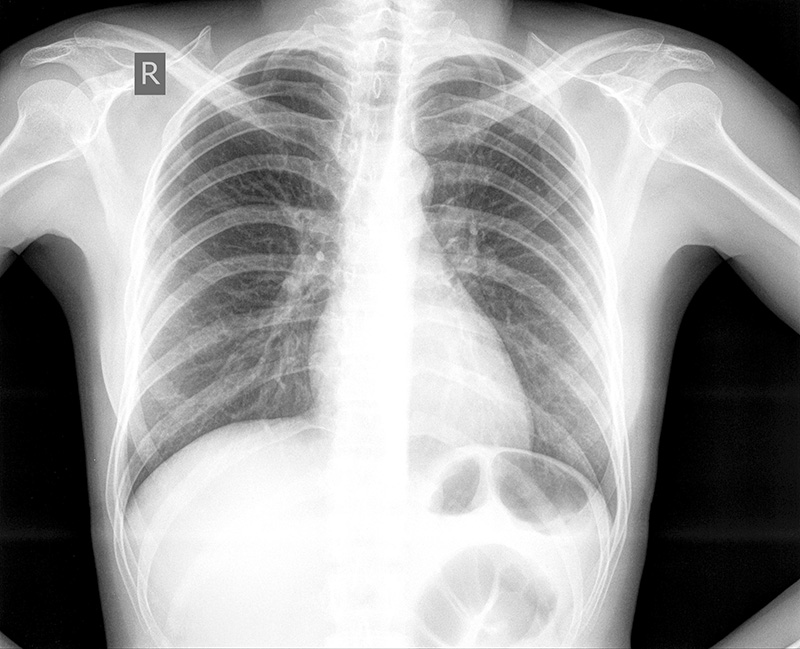

На обзорной рентгенограмме органов грудной клетки в прямой проекции – грудная клетка обычной формы. Легочные поля прозрачные, легочной рисунок не усилен. Корни легких не расширены, структурные. Синусы свободные, Купола диафрагм ровные. Рёберные промежутки не расширены, расположение ребер обычное, слева имеется перелом 5-го ребра по подмышечной линии без смещения. Тень сердца обычной формы, в поперечнике не расширено, аорта не широкая, уплотненная в области дуги - краевой кальциноз.

1. ОГК без патологии

6. Рентгенография органов грудной клетки-2-х сторонняя пневмония

8. Рентгенография органов грудной клетки- гидропневмоторакс ! слева, подкожная эмфизема